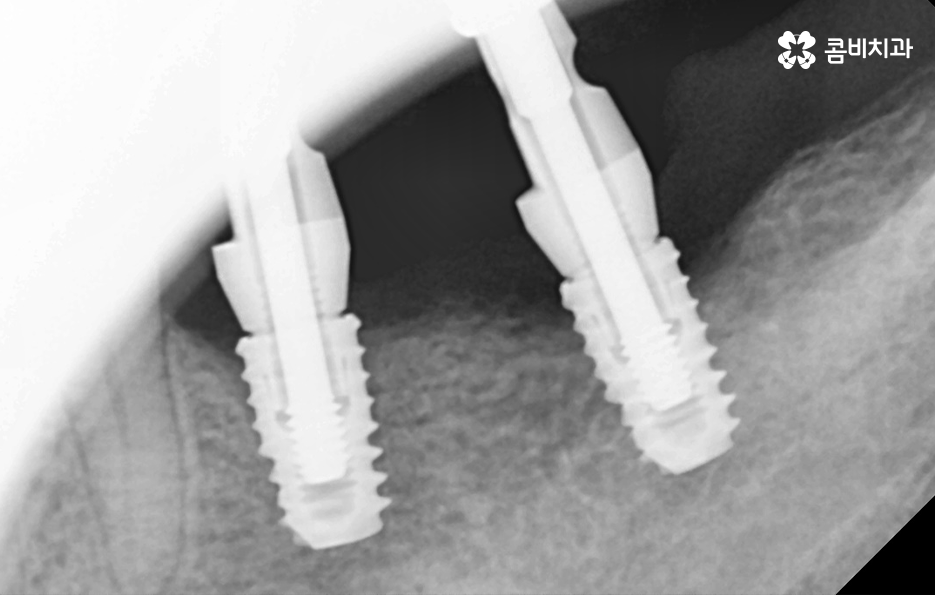

오늘 보시는 포스팅에서의 치료 과정도 어금니에 임플란트가 필요한 상태에서 윗니를 보시면 윗니가 다소 벌어진 것을 확인할 수 있는데요. 교정 하면 보통 전체교정을 떠올리게 되긴 하지만 경우에 따라서는 치열이 전체적으로 가지런한 편인데 앞니가 살짝 벌어진 경우나 어금니만 다소 벌어진 경우도 있을 거예요

이러한 경우에는 부분교정을 통해서 다소 개선이 필요한 치열을 가지런하게 만들고 가지런해진 치열과 교합 상태에 적합한 임플란트 치료 계획을 세워서 치아의 심미성과 기능적인 부분, 얼굴과의 조화를 종합적으로 고려하여 좋은 결과를 얻을 수 있어요